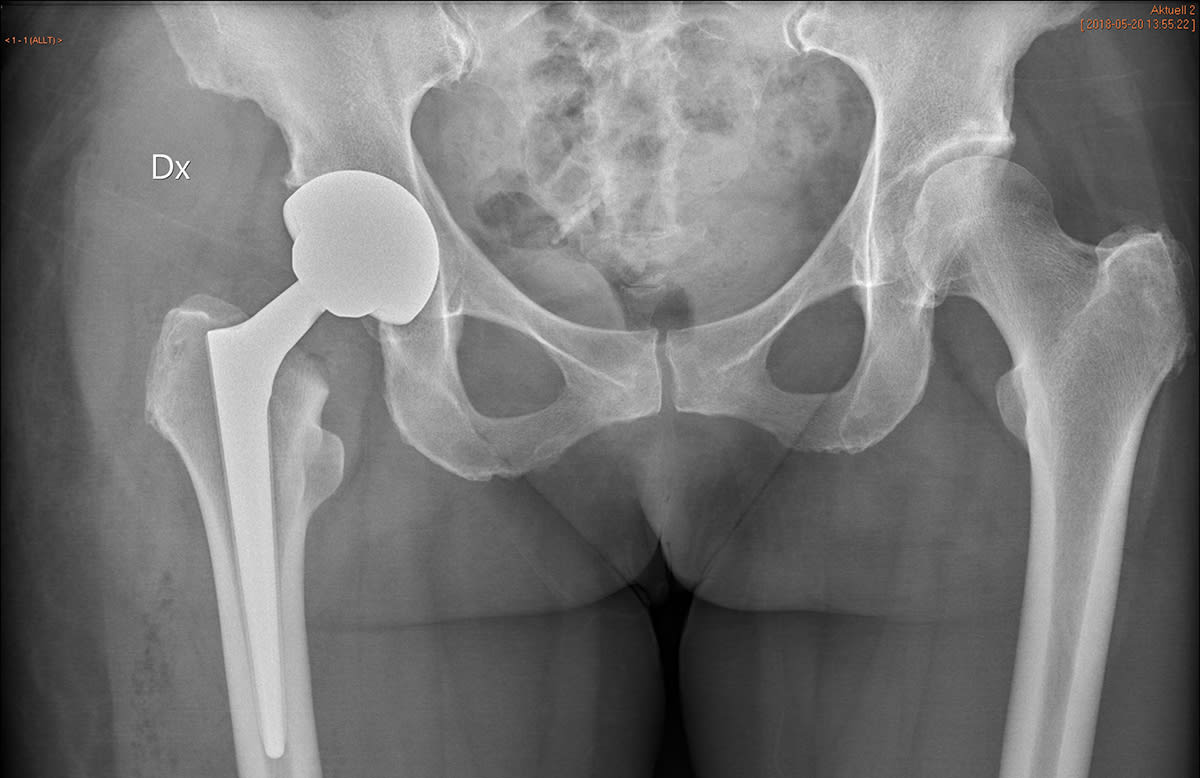

Röntgenbilden visar ett bäcken där patienten på ena sidan (vänster i bild) fått en höftprotes inopererad.